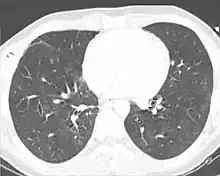

Chest X-ray is the most common method used for diagnosis,[37] and may be used to confirm a diagnosis already made using clinical signs.[20] Consolidated areas appear white on an X-ray film.[42] Contusion is not typically restricted by the anatomical boundaries of the lobes or segments of the lung.[27][43][44] The X-ray appearance of pulmonary contusion is similar to that of aspiration,[32] and the presence of hemothorax or pneumothorax may obscure the contusion on a radiograph.[25] Signs of contusion that progress after 48 hours post-injury are likely to be actually due to aspiration, pneumonia, or ARDS.[10]

Although chest radiography is an important part of the diagnosis, it is often not sensitive enough to detect the condition early after the injury.[35] In a third of cases, pulmonary contusion is not visible on the first chest radiograph performed.[7] It takes an average of six hours for the characteristic white regions to show up on a chest X-ray, and the contusion may not become apparent for 48 hours.[7][27][43] When a pulmonary contusion is apparent in an X-ray, it suggests that the trauma to the chest was severe and that a CT scan might reveal other injuries that were missed with X-ray.[2]